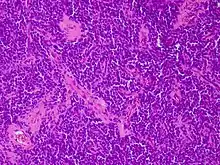

Los tumores vaginales son neoplasias que se encuentran en la vagina. Pueden ser benignos o malignos.[1] Una neoplasia es un crecimiento anormal de tejido que generalmente forma una masa de tejido.[2][3][4] Las neoplasias vaginales pueden ser sólidas, quísticas o de tipo mixto.[5]

Los cánceres vaginales surgen del tejido vaginal, y los sarcomas vaginales se desarrollan a partir de hueso, cartílago, grasa, músculo, vasos sanguíneos u otro tejido conjuntivo o de soporte.[6][7] Los tumores en la vagina también pueden ser metástasis (tejido maligno que se ha diseminado a la vagina desde otras partes del cuerpo).[8][7] El cáncer que se diseminó desde el colon, vejiga y estómago es mucho más común que el cáncer que se origina en la vagina.[9] Algunos tumores benignos pueden progresar hasta convertirse en tumores malignos, como los cánceres vaginales.[10][11] Algunos tumores neoplásicos de la vagina son lo suficientemente raros como para describirse solo en estudios de casos.[3]